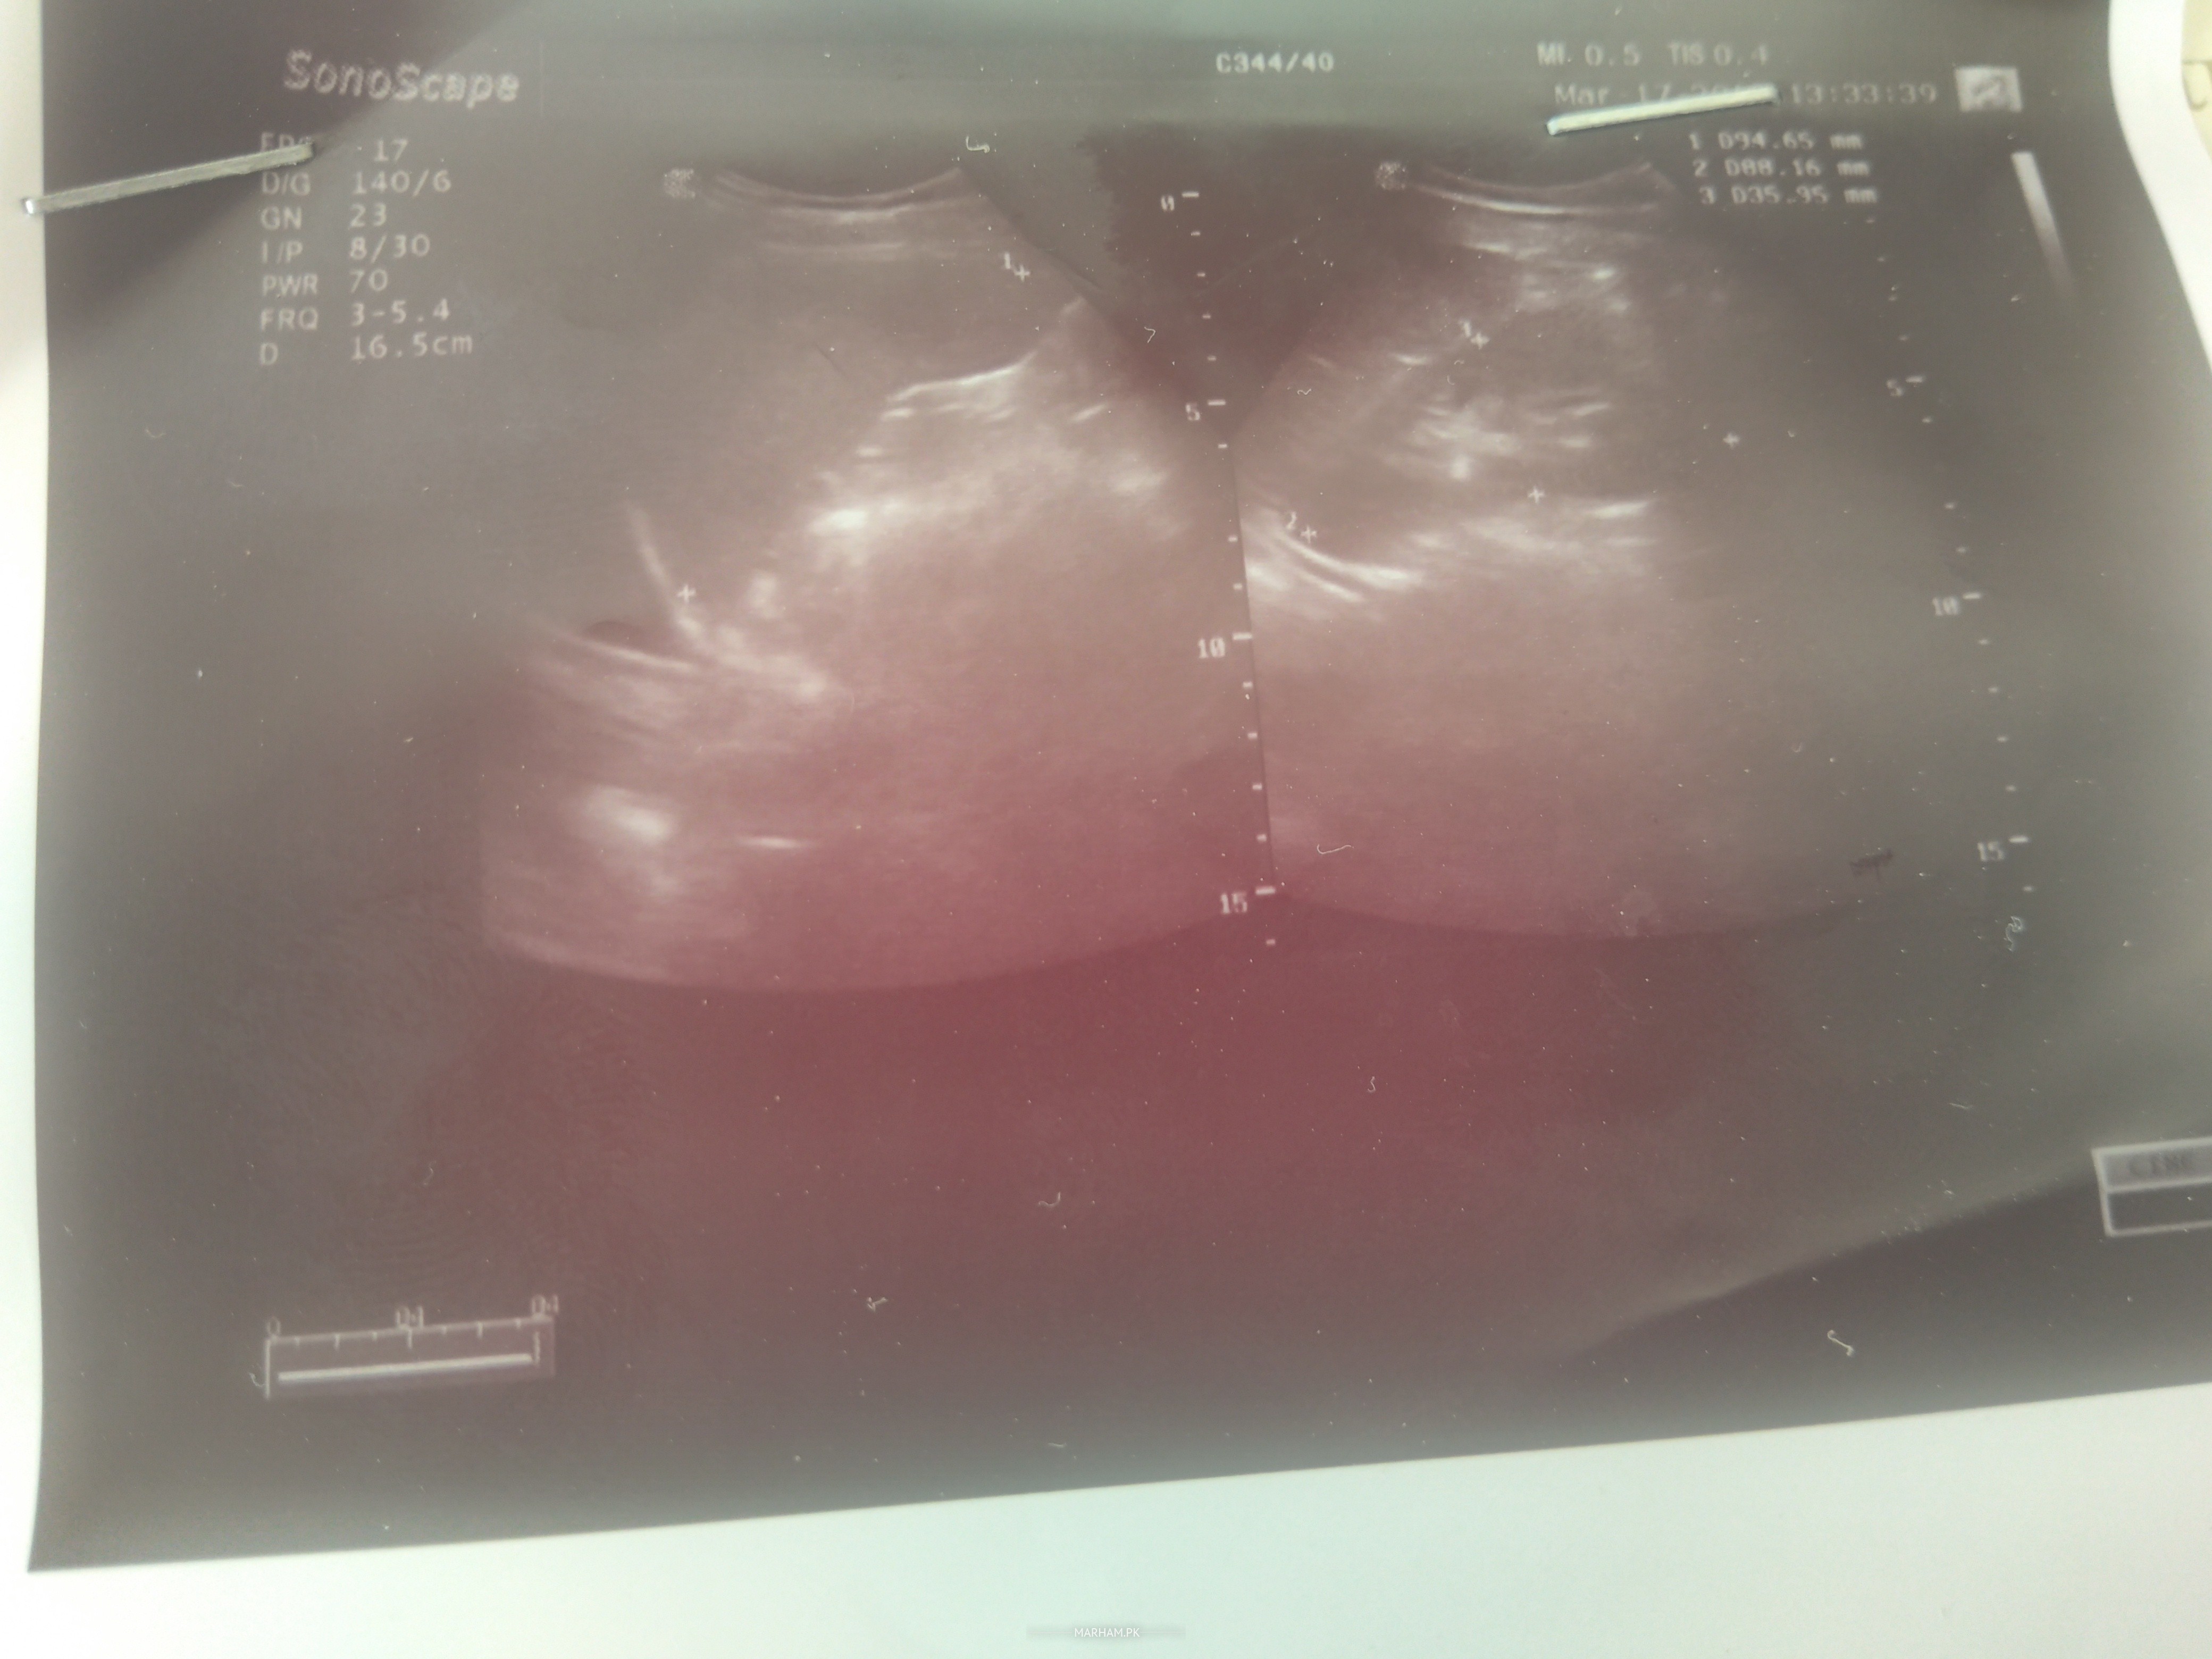

hi.. i am having vaginal itching for some months... and a discharge as well. it's been a week i have severe abdominal pain and swelling with fever and fatigue. i went to my ultrasound.. it says that i have infection in pelvis area... most probably PID. i am attaching Ultrasound report... i am unmarried.. i went to gyny with these reports but she said.. it's not a big the other hand the doc who took my ultrasound says that this is serious infection and it is affecting other parts. suggestions please.